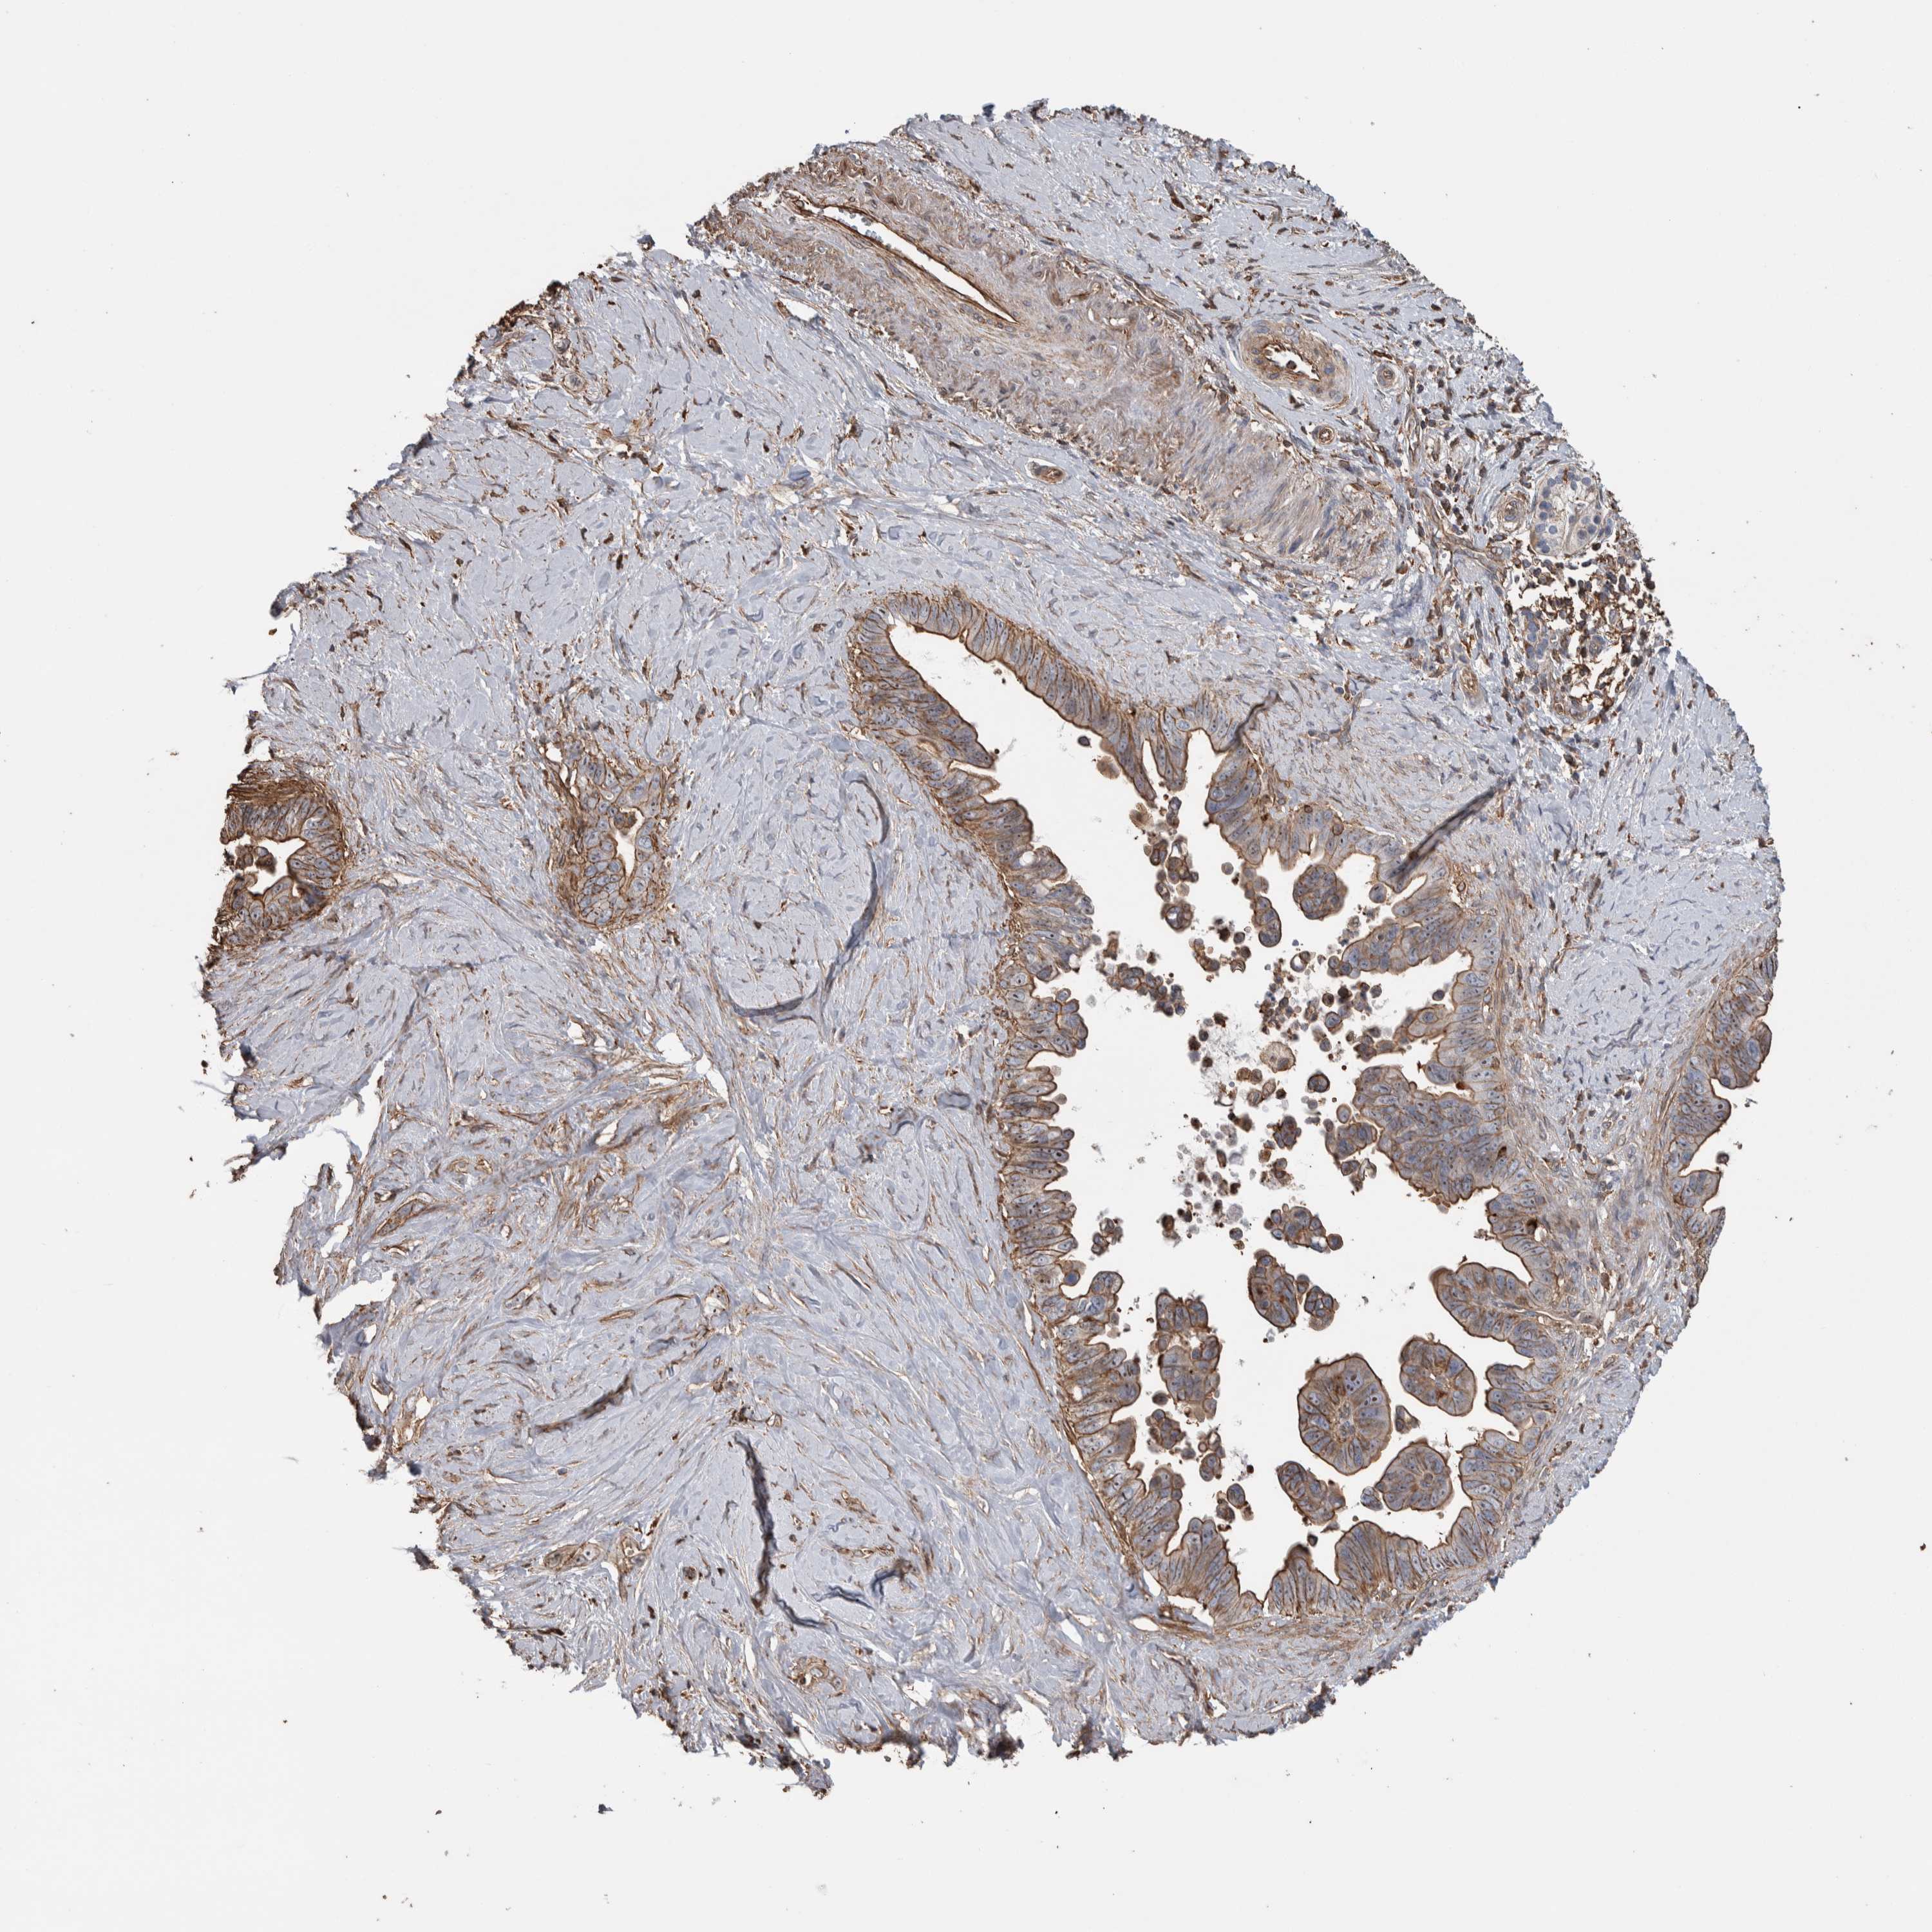

PANCREATIC CANCER - Protein expressioni

A mouse-over function shows sample information and annotation data. Click on an image to view it in a full screen mode. Samples can be filtered based on level of antibody staining by selecting one or several of the following categories: high, medium, low and not detected. The assay and annotation is described here.

Note that samples used for immunohistochemistry by the Human Protein Atlas do not correspond to samples in the TCGA dataset.

Antibody stainingi

Antibody staining in the annotated cell types in the current human tissue is reported as not detected, low, medium, or high, based on conventional immunohistochemistry profiling in selected tissues. This score is based on the combination of the staining intensity and fraction of stained cells.

Each image is clickable and will lead to virtual microscopy that enables deeper exploration of all samples and also displays staining intensity scores, fraction scores and subcellular localization as well as patient and tissue information for each sample.

Antibody HPA023700

Staining

High

Medium

Low

Not detected

Intensity

Strong

Moderate

Weak

Negative

Quantity

>75%

75%-25%

<25%

None

Location

Nuclear

Cytoplasmic/membranous

Cytoplasmic/membranous,nuclear

Adenocarcinoma, NOS